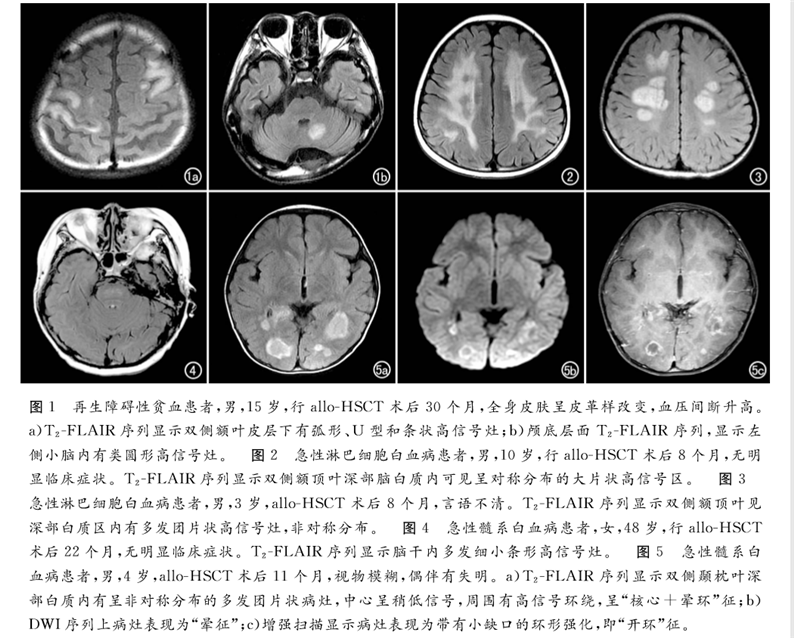

北京陸道培醫(yī)院影像科發(fā)表題為《血液病異基因造血干細(xì)胞移植后中樞神經(jīng)系統(tǒng)慢性移植物抗宿主病的MRI表現(xiàn)》的論文,該論文刊登在中文特種醫(yī)學(xué)類核心期刊《放射學(xué)實(shí)踐》2019年12月第34卷第12期。

論文回顧性分析了2013年6月—2017年12月北京陸道培醫(yī)院確診為allo-HSCT后并發(fā)中樞神經(jīng)系統(tǒng)慢性移植物抗宿主病的12例血液病患者的臨床和影像學(xué)資料。得出結(jié)論,MRI是發(fā)現(xiàn)血液病異基因造血干細(xì)胞移植(allo-HSCT)后并發(fā)中樞神經(jīng)系統(tǒng)慢性移植物抗宿主病的有效手段,可以提高對(duì)本病的診斷及鑒別水平,為臨床制訂佳治療方案提供幫助。